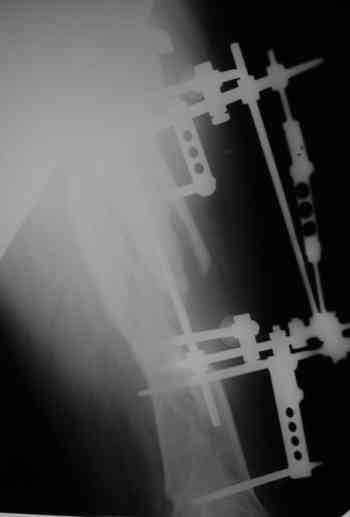

Уважаемые коллеги! Пришел на консультацию вот такой больной (первые 3-и рисунка). Травма автодорожная, апрель 2006г. Лечился консервативно, вытяжение и гипс. Через пять месяцев стал ходить. Укорочение бедра 6 см. 26 февраля 2007г. оступился, упал. Прооперирован в г.Баку - наложен стержневой аппарат. Ходит с костылями, наступая на левую ногу. Мы попросили что нибудь из ранних снимков. Принес рентгенограммы перелома (рис. 4,5). Посмотрели, наснимали сами (рис. 6-10). Похоже, что нет сращения нигде. Хотелось - бы обсудить следующие вопросы:1. дальнейшая тактика - реостеосинтез или подождать (ослабить аппарат, дать нагрузку и т.д.)?2. если реостеосинтез - то чем и как? Юрий Алексеевич Булахтин

Лучше бы закрытый интрамедуллярный, конечно.

Надо делать чрескожную подвертельную остеотомию, чтобы получился открытый клин. Проблемы будут и с формированием канала, надо развертки типа наших. Был как-то похожий случай, сделали одномоментно, сняли аппарат 5-месячый на столе, заштифтовали с подвертельной остеотомией (в приложении).

Можно все коррекции сделать и в аппарате, и потом заштифтовать, тогда останется только одна проблема формирования канала.